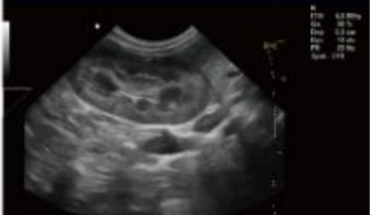

Fonction d'application clinique riche

- Technologie d’imagerie composée spatiale

- Technologie d'imagerie panoramique (Facultatif)